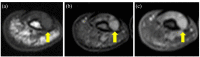

An association between glomus tumor and neurofibromatosis type 1 has been reported. It is characterized by multiple tumors and young age at onset. The early diagnosis of neurofibromatosis type 1 is important because it is associated with a high rate of malignancy. A 25-year-old man presented to our hospital with left index finger pain that had persisted for 6 years. Physical and imaging findings suggested a benign soft-tissue tumor. Surgery was performed, and the tumor was pathologically diagnosed as glomus tumor. In this case, the patient with a young-onset glomus tumor was suspected of having neurofibromatosis type 1. An additional medical examination led to the diagnosis of unrecognized neurofibromatosis type 1. We experienced a case in which the onset of a glomus tumor led to the diagnosis of neurofibromatosis type 1. Comorbid neurofibromatosis type 1 should be kept in mind when glomus tumors are diagnosed.